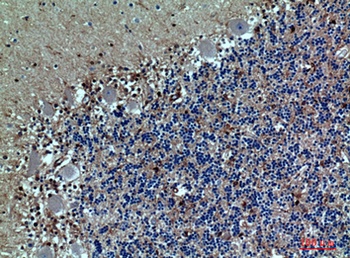

Formalin-fixed, paraffin-embedded human Tonsil stained withCD162 Monoclonal Antibody (PSGL1/1601).